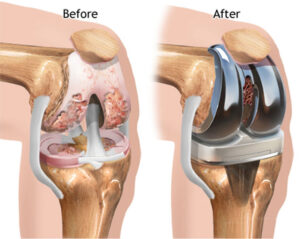

Surgical treatment is usually saved for when conservative treatments have been exhausted and the patient’s symptoms severely limit their function. The most typical and best surgical treatment is currently a total joint arthroplasty, or total joint replacement. In this procedure, the arthritic surfaces of the articulating joint are replaced with artificial materials. Outcomes of total knee replacement are very good, and increasingly better when individuals combine surgery with post-operative physical therapy rehab. If you are contemplating this type of procedure, be sure to come in and get a physical therapy evaluation prior to the procedure so that you can start on rehab exercises immediately after surgery. The quicker you start physical therapy, the better your outcomes will be.